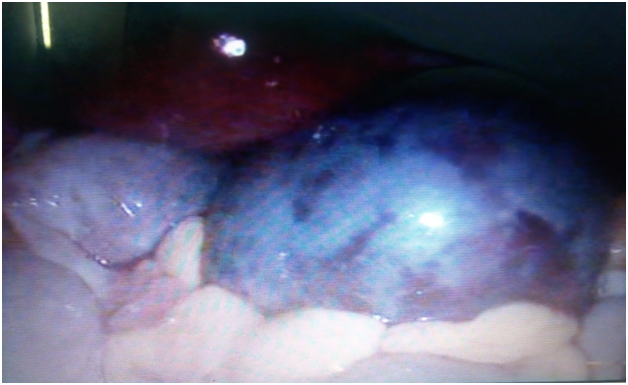

Intraoperatively, right adnexa was twisted for three and half turns on its pedicle and appeared bluish black, edematous and congested suggestive of haemorrhagic necrosis. Following detorsion, right tube immediately gained colour and the right ovary also began to regain its colour slowly in the periphery. On attempting cystectomy, cyst ruptured and drained hemorrhagic fluid, the surrounding ovarian tissue was highly edematous and friable. Cystectomy was done with removal of the surrounding blackish and friable tissue. Rest of the ovary near the hilum was preserved despite, it appearing bluish-black and edematous. Left ovary was enlarged with multiple small follicles and a 3x2 cm haemorrhagic cyst was found which was also excised. Post operative period was uneventful and the patient was discharged the next day with a 5 day course of antibiotics and analgesics. A follow up scan was done after 6 weeks which revealed remnant ovarian tissue on the right side along with good follicular activity and normal blood flow (Figures 1-3).

Figure 1 laparoscopic view of the necrotic and hemorrhagic ovary following torsion.